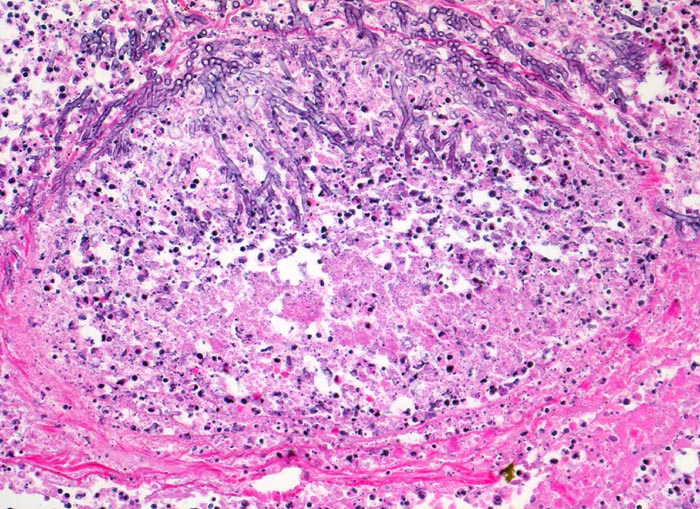

Aspergilluspneumonie

Entzündung infektiös

Lunge

Gewebsnekrose durchsetzt von zerfallenden neutrophilen Granulozyten (die schwarzen Punkte entsprechen den Kerntrümmern der neutrophilen Granulozyten). In der Nekrose sind schlanke Pilzhyphen mit 45° Verzweigungen erkennbar.

Seit 14 Monaten bekannte chronische lymphatische Leukämie behandelt mit Chemotherapie. Der Patient entwickelt unter Therapie eine Pneumonie und verstirbt an einer Pilzsepsis.

200